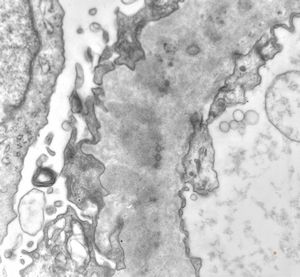

M,29y. | type II membranoproliferative glomerulonephritis (dense deposit disease)